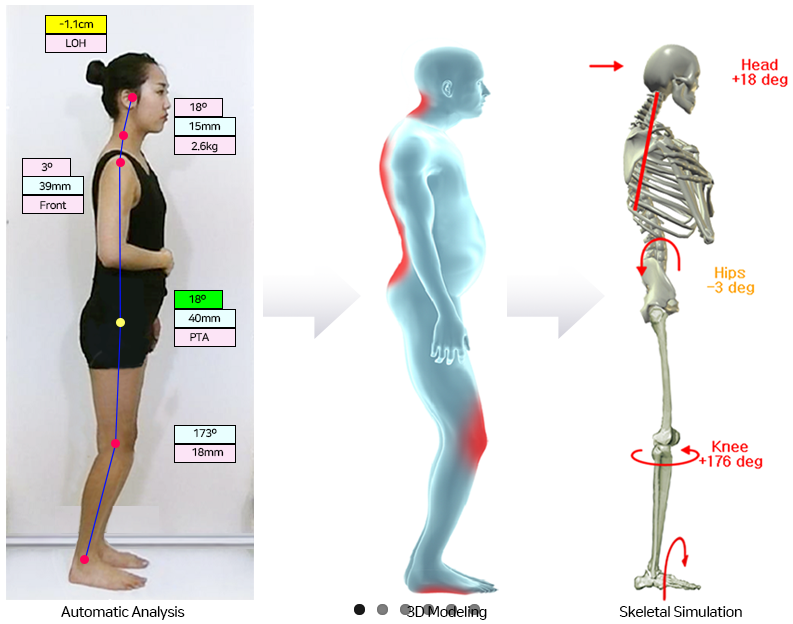

虽然体态评估并没有限定是在哪种体态下进行评估,也没有限定是静态还是动态,但我们一般认为体态评估指的是静态站姿评估。站姿中透露了很多关于身体姿势维持的信息,而且是整体性的信息。

2、为什么要进行体态评估

① 体态评估能帮助我们更好的了解自己先看下面这张图片里的姑娘。如果没有铅垂线和网格图,我们可能会觉得体态上没有什么问题,但根据图上显示,很明显左右两侧不对称,而且 头前倾 、骨盆轻微前倾。

很多有体态问题的人,其实很早就已经有所感知了,可能是酸胀,可能是呼吸受限,也可能是疼痛。但由于这些 现象 的出现是慢性的,在早期,发作时也不会太剧烈,所以往往都没有引起足够重视,一般都是以太累了或者最近运动太少了作解释。

如果能在身体有异常感知的时候,就能进行体态评估,那么可能可以更早地明确问题所在,从而有针对性地去解决。所谓上医治未病就是这个道理。另外,即便在 症状 已经很严重的时候,进行体态评估能够更全面地了解自己的身体,给治疗提供更丰富的信息。

② 体态评估简单易行尽管完整的体态评估需要专业人士的指导和协助,但自我评估也能对一些常见的体态问题进行筛查,而且在家中就能完成。

3、体态评估的 4 个原则

① 要拍照由于体态维持是动态的,即便是在静止站立的状态下,仍然有微小的动作。通过拍照的方法,记录瞬间的体态表现,可以在照片上划线、测量距离和角度,因此能够更好地评估和分析。

② 要在自然状态下评估

我们在 日常生活 中,各种体态的维持都是下 意识 的,比如当我们自然站立时,我们不会刻意收缩哪块肌肉来保持平衡。那么为了更准确地反映我们的真实状态,在下意识的状态下进行评估是很必要的。

有些小伙伴在给发自己的体态照片时,会用透过镜子自拍的方式,先不论拿着手机或相机会对体态造成影响,当我们照镜子时,我们会根据 视觉 的反馈 调整 我们的体态,就是说镜子里的我们并不是真实的样子。

还有一些小伙伴在拍摄体态照片时,会有意的抬头挺胸,更有甚者,会让给自己拍照的人提醒她应该怎么调整,毕竟让自己看起来更美是人之常情,但出于准确评估的目的,我们还是要尽可能地保持自然状态。

4、体态自我评估方法人的动作可以在三个动作面上进行,即矢状面、冠状面和 水平 面,如下图所示:

观察人的身体有 4 个角度:正面、背面和两个侧面,不同的角度观察的 内容 不同,也因此能发现不同的体态问题。

体态观察点

体态观察是通过几个关键的解剖点的排列来判断体态表现,常用的观察点请见下表。

注:上图中为了展示清楚,骨骼模型采用解剖学站姿,实际做体态观察时, 手臂 自然下垂即可。

② 拍照须知

如前文所言,我们体态观察是根据照片来进行的。关于拍照,请注意以下几点。

①通过侧面观察的体态问题

通过侧面观察,我们能发现自己在矢状面(前后) 的体态问题。正常状态下,人类 的身体中这五个点应该近似位于一条直线的:耳垂、肩峰、股骨大转子、股骨外髁、外踝。

由于人类的大量运动是在矢状面进行的,因此从侧面观最容易发现体态问题,所以我们一般会以侧面观察作为体态评估的开始 。人体的五个主要关节在矢状面的功能紊乱会导致一系列的代偿现象,常见的矢状面体态问题包括骨盆前倾、骨盆后倾、圆肩探头、驼背等。